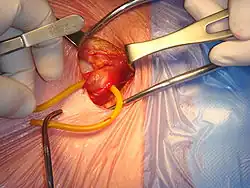

Reparación quirúrgica de una hernia inguinal derecha | ||

La cirugía de la hernia inguinal es una operación quirúrgica para la corrección de una hernia inguinal. No se recomienda la cirugía en la mayoría de los casos, y la espera vigilante es la opción recomendada.[1][2] En particular, la cirugía electiva ya no se recomienda para el tratamiento de hernias mínimamente sintomáticas, debido al riesgo significativo (> 10%) de dolor crónico ( síndrome del dolor post herniorrafia) y el bajo riesgo de encarceración o estrangulamiento (<0,2% por año).[3] Como consejo general si se opta por la cirugía, son más importantes la elección del cirujano y del hospital que la de una determinada técnica o material quirúrgico.[4]